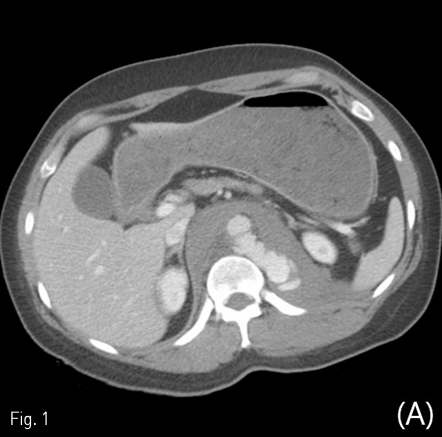

전산화단층촬영에서 자상으로 인해 대동맥에 거짓동맥류와 이와 관련한 광범위한 후복강 혈종이 보이고 있음 (Fig. 1A, B). 거짓동맥류가 생긴 위치는 복강동맥이 기시하는 높이의 뒤쪽 왼쪽인 5시 방향이었음. 이와 연관된 혈종은 후복강의 대동맥 주변과 횡격막 다리의 뒤쪽을 따라 연장되어 있었음. 그 외 다른 흉강이나 복강내 장기의 손상은 동반되지 않았음.

Fig 1A

Contrast-enhanced axial (A), coronal (B) CT scan demonstrates ruptured pseudoaneurysm (arrows) at posterior aspect of abdominal aorta causing redundant hemoretroperitoneum.